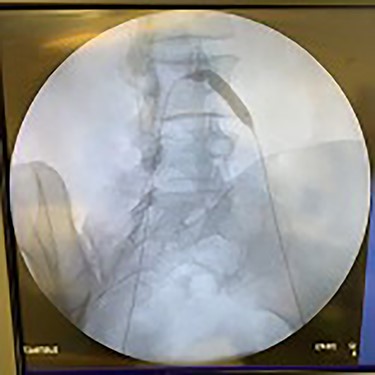

Catheter arteriogram results showed significant occlusion of the left iliac artery (Figs 3 and 4), the right iliac artery (Fig. 1), as well as the distal abdominal aorta (Fig. 2). There were numerous collateral vessels noted, indicating the presence of long-standing proximal stenosis (Fig. 1). The decision was made to use angioplasty to help widen the areas of stenosis. An 8 mm × 40 mm Passeo balloon was advanced from the right femoral artery into the left iliac artery (Fig. 7) and insufflated to 6 mmHg (Fig. 6). The balloon was allowed to remain expanded for 1 min and then was deflated. Next, the distal aorta was repaired in a similar fashion. The balloon was advanced into the distal aorta from the right femoral access and insufflated to 12 mmHg (Fig. 8). The balloon was allowed to remain expanded for 90 s.

Fluoroscopy of bilateral iliac arteries showing significant arterial disease.